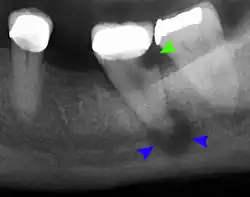

The periodontal ligament becomes inflamed and there may be pain when biting or tapping on the tooth. On an X-ray, bone resorption appears as a radiolucent area around the end of the root, although this does not manifest immediately.[10]: 228 Acute apical periodontitis is characterized by well-localized, spontaneous, persistent, moderate to severe pain.[6]: 125–135 The alveolar process may be tender to palpation over the roots. The tooth may be raised in the socket and feel more prominent than the adjacent teeth.[6]: 125–135

- Radiographs utilized to find dental caries and bone loss laterally or at the apex.

Decay (green) with apical abscess (blue) -

Gutta-percha point indicating abscess origin